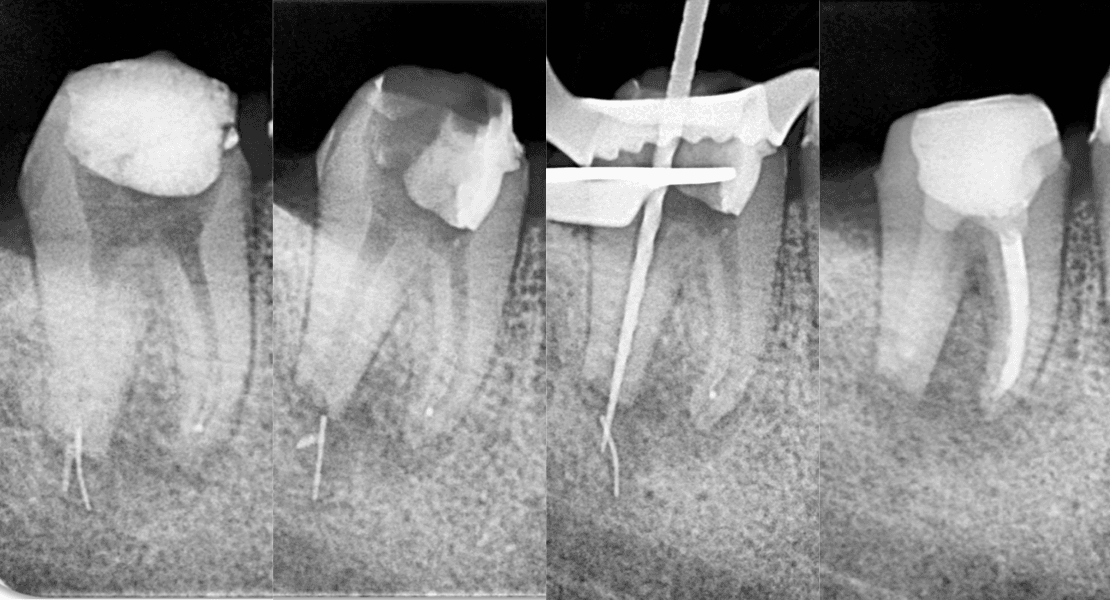

🥇 Uzm. Dt. Yahya Güven

Kök Ucundan Taşmış Kırık Eğeye Sahip Alt Çene Büyükazı Dişinin Endodontik Yönetimi